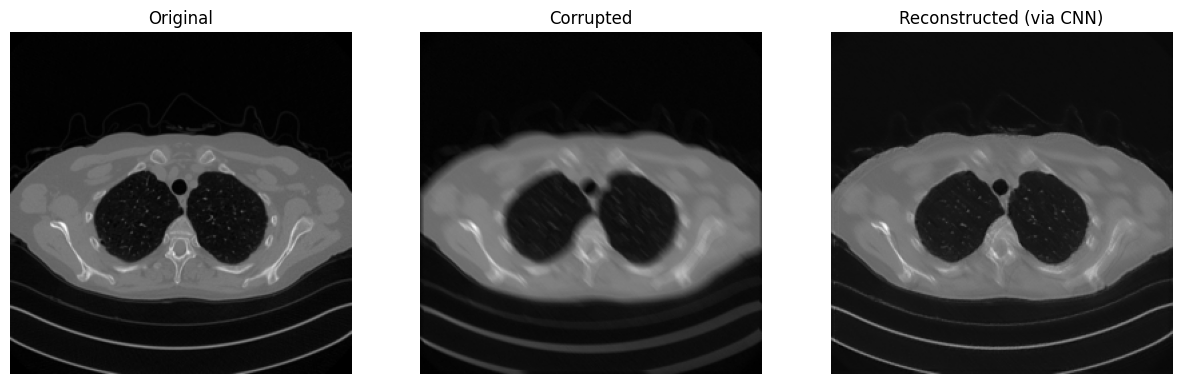

print(f"SSIM: {metrics.SSIM(x_rec.cpu(), x_true.cpu()):0.4f}")

# Visualize

plt.figure(figsize=(15, 5))

plt.subplot(1, 3, 1)

plt.imshow(x_true.detach().cpu().squeeze(), cmap='gray')

plt.axis('off')

plt.title('Original')

plt.subplot(1, 3, 2)

plt.imshow(y_delta.detach().cpu().squeeze(), cmap='gray')

plt.title('Corrupted')

plt.subplot(1, 3, 3)

plt.imshow(x_rec.detach().cpu().squeeze(), cmap='gray')

plt.title('Reconstructed (via CNN)')

plt.show()

Shape of x_true: torch.Size([1, 1, 256, 256]). Range of x_true: (tensor(0.), tensor(0.9348))

SSIM: 0.9409

../_images/4a40ce52bb03d8e71a3b2ec8a9ebde6c8babd15061266477e8a8d1bbcc29a057.png